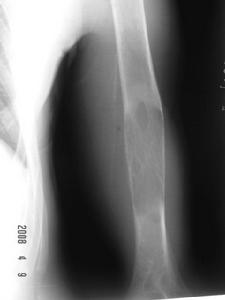

腓骨骨腫瘤X線表現一、放射學檢查

X線檢查對明確骨腫瘤性質、種類、範圍及決定治療方針都能提供有價值的資料,是骨腫瘤重要的檢查方法。然而X線片僅是骨腫瘤的投影,骨腫瘤的X線表現不恆定,需密切結合臨床表現和病理檢查,才能作出準確診斷。

良性骨腫瘤形態規則,與周圍正常骨組織界限清楚,以硬化邊為界,骨皮質因膨脹而變薄,但仍保持完整,無骨膜反應,惡性腫瘤的影像不規則,邊緣模糊不清,溶骨現象較明顯,骨質破壞,變薄,斷裂,缺失,原發性惡性腫瘤常出現骨膜反應,其形狀可呈陽光放射狀,蔥皮樣及Codman三角。

2、腫瘤對宿主骨的影響 腫瘤與宿主骨間邊界有無浸潤性是確定病變性質的首要因素,邊界清楚者表明腫瘤生長緩慢且浸潤性弱。反之,邊界模糊者則表明腫瘤浸潤性強。

3、宿主對腫瘤的反應 宿主總是力圖消滅腫瘤,將其包裹,形成纖維組織包膜,生長快速的腫瘤可浸潤和破壞這種反應性骨包膜,而僅在腫瘤的一端或兩端能見到這種包膜的殘餘,通常表現為Codman三角。

4、腫瘤組織的密度 骨組織顯像中如有任何密度變化,均可懷疑該組織有病變,有些腫瘤為溶骨性病變,如骨巨細胞瘤,而有些為成骨性病變,成骨不規則或為雪花狀,如骨肉瘤、軟骨肉瘤。